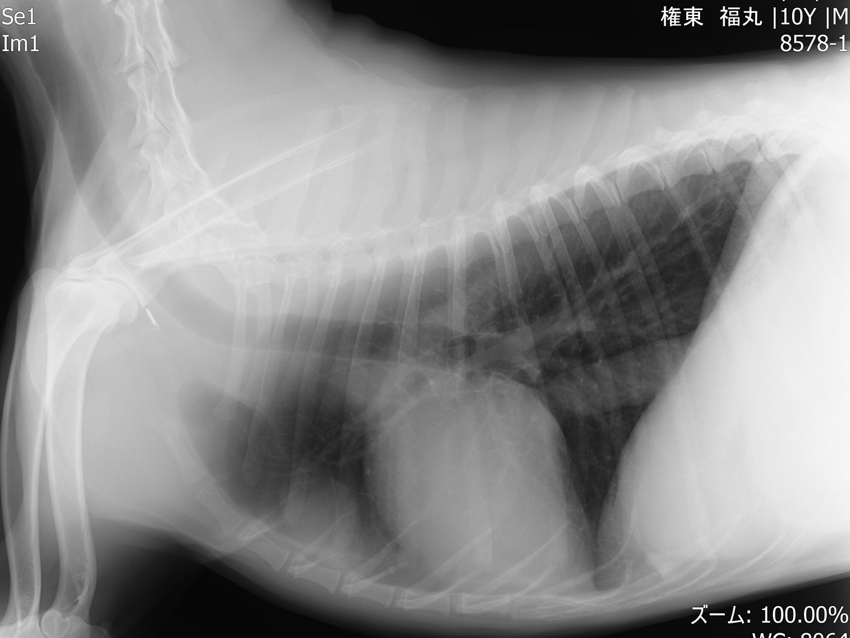

他疾患の手術前検査として実施した胸部レントゲン検査にて、前縦隔部に腫瘤性病変を認めたことから、精査のためCT検査を実施しました。 CT所見より、胸腺腫や異所性甲状腺腫瘍などの腫瘍性疾患が強く疑われたため、胸腔鏡を用いた腫瘤摘出術を行いました。 術前より臨床症状は認められず、全身状態も良好であったため、術後の経過は順調であり、術後2日目に退院となりました。

手術前のレントゲン画像

術後のレントゲン画像写真